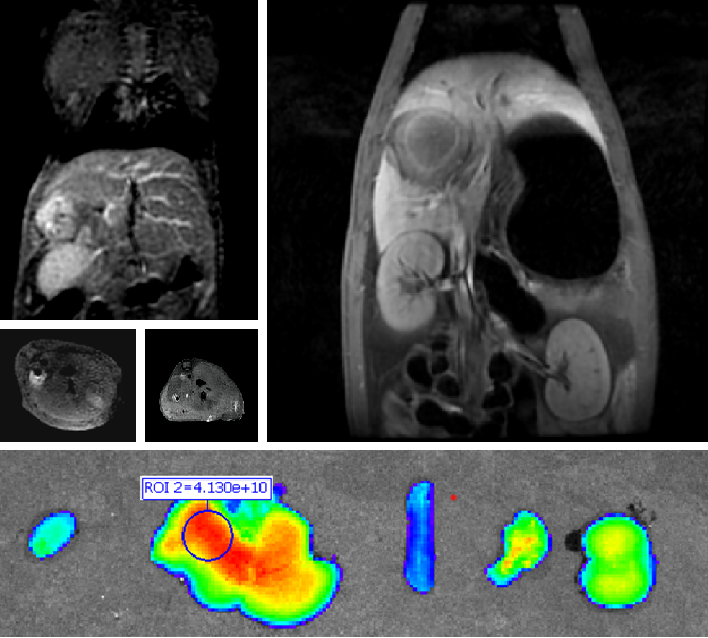

PL002是浙江普利药业有限公司研发的荧光/磁共振双模态造影剂,开发荧光/磁共振双模态造影剂成为提高原发性肝癌手术效率的有效方案。双模态造影剂的荧光成像能力可用于肝癌术中荧光导航,而磁共振增强能力可用于在术前判断肝脏代谢能力,推测肿瘤及肝脏对造影剂的摄取情况,提高肿瘤诊断精度,降低术前规划难度。

PL002相较于吲哚菁绿具有明显优势。目前吲哚菁绿在临床使用中存在给药到手术时间不确定的问题,可能造成病灶与正常组织对比度不足,影响术中的病灶的判断,PL002采用独特的钆络合物与荧光分子共价键结合的分子结构设计,这种设计能够让医生在术前通过磁共振成像确定造影剂在病灶中的聚集情况,进而针对患者个体情况来对手术时间进行规划。同时,由于PL002体内更为稳定,在荷瘤小鼠模型中同等条件下荧光成像效果维持时间长于现有荧光造影剂,也保证了其在临床应用中具有更宽的手术窗口。

使用双模态造影剂可以为手术医生提供更加丰富的诊断信息,降低术中的决策压力,避免过度切成,增加发现微小病灶的可能性,最终实现患者的全面获益。此外,相较于传统荧光造影剂,PL002的安全性更高、体内更为稳定,成像效果更佳,为其临床使用提供了有效的支持。